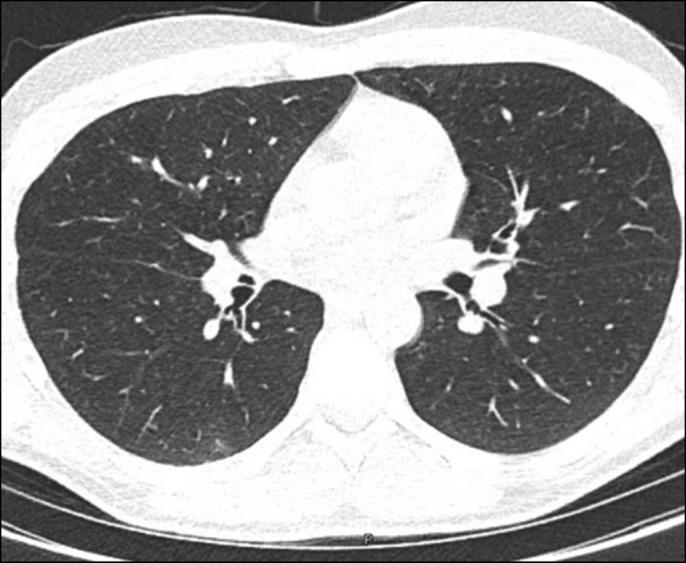

Necrobiotic pulmonary nodules are an exceptionally rare extraintestinal manifestation of inflammatory bowel disease. Recognition is imperative because it may mimic other autoimmune pathologies such as granulomatosis with polyangiitis or sarcoidosis. We describe a 19-year-old man with a known history of ulcerative colitis who was found to possess bilateral pulmonary nodules on computed tomography imaging. Investigations that included an extensive autoimmune and infectious workup were inconclusive. Biopsy of the nodules revealed fibrinous exudate and palisading histiocytes that confirmed the diagnosis. He was started on prednisone therapy. A follow-up computed tomography a month later revealed near complete resolution.

坏死性肺结节是炎症性肠病一种极其罕见的肠外表现。必须认识到这一点,因为它可能会模仿其他自身免疫性疾病,如肉芽肿性多血管炎或结节病。我们描述了一名19岁有溃疡性结肠炎病史的男性,其在计算机断层扫描成像中发现有双侧肺结节。包括广泛的自身免疫和感染检查在内的各项检查均无定论。结节活检显示有纤维蛋白渗出物和栅栏状组织细胞,从而确诊。他开始接受泼尼松治疗。一个月后的随访计算机断层扫描显示几乎完全消退。